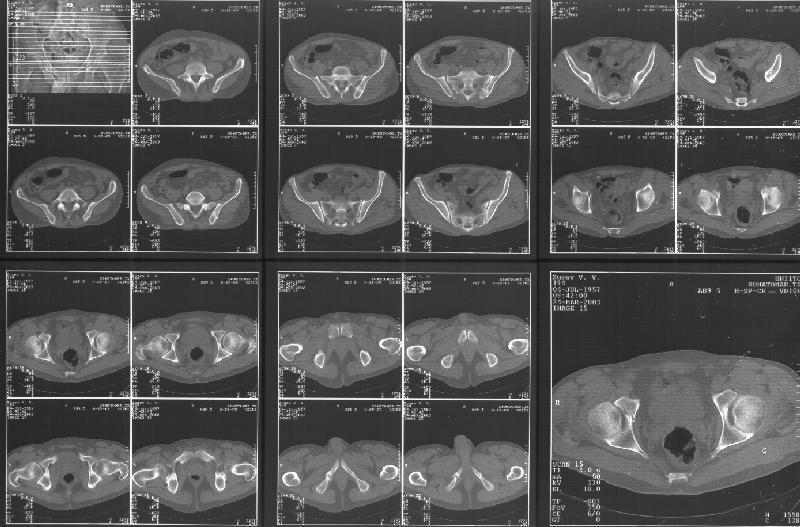

Прилагаю свежую КТ таза.

Буду признателен за комментарии и предложения по тактике.

Картинки см. ниже, левая - с экранным разрешением, вторая - полноразмерная, ~900 кб.

КТ в экранном разрешении

Полноразмрная картинка, около 900 кб